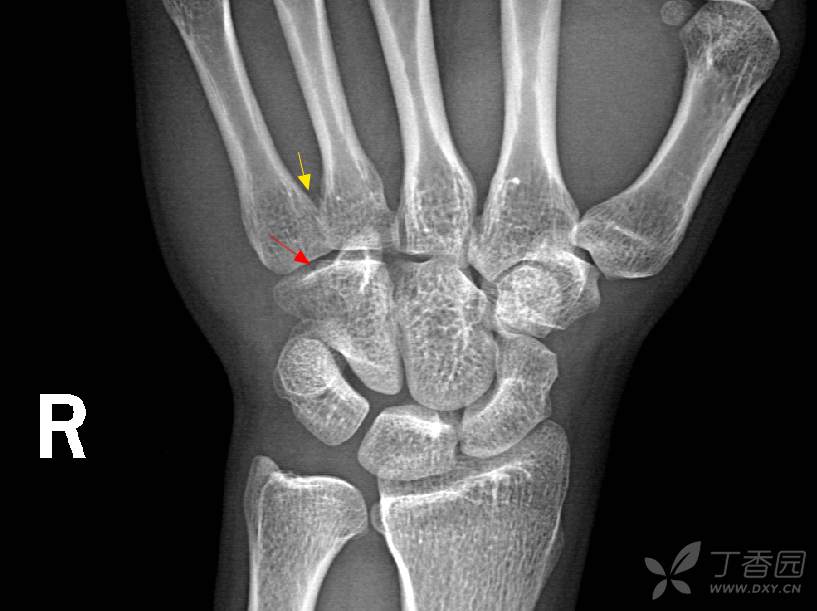

腕关节正位片

腕关节正侧位片

腕关节x线高清解剖图谱-最基础实用!

腕关节侧位x线图片

正常腕关节x片图